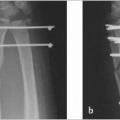

Scaphoid waist fracture (► Fig. 4.1)

Acute or chronic fracture line as above.

Significant bone marrow edema around the fracture line.